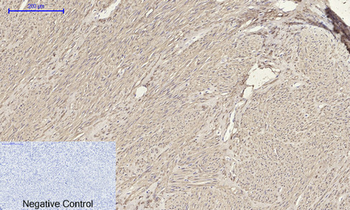

100 μlACTA2 Antibody [orb395590]

ELISA, IF, IHC, WB

Human, Mouse, Rat

Rabbit

Polyclonal

Unconjugated

100 μg, 50 μgACTA2 Antibody [orb624472]